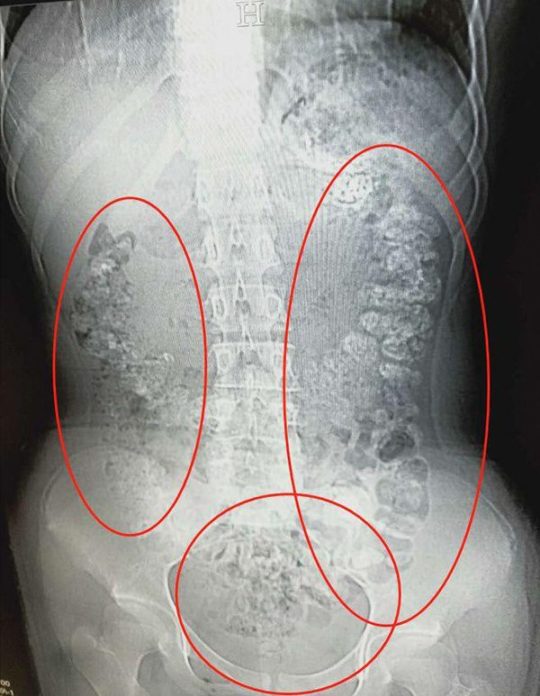

เว็บไซต์ข่าวคมชัดลึก นำเสนอข่าวจากหนังสือซินชิว และเดอะเปเปอร์ รายงานว่าเมื่อวันที่ 28 พ.ค. ที่ผ่านมา พบ เด็กหญิงวัย 14 ปีในมณฑลเจ้อเจียง ประเทศจีน ถูกนำตัวส่งแผนฉุกเฉินหลังมีอาการปวดท้องหนัก ลักษณะท้องบวมเป่ง และขับถ่ายไม่ออกมาหลายวัน เมื่ออัลตร้าซาวด์พบเม็ดไข่มักเป็นร้อยๆเม็ด เรียงตัวอยู่ในระบบทางเดินอาหาร

หลังการรักษา นายแพทย์ จาง หลัว เว่ย ได้สอบถามถึงพฤติกรรมการกินของเด็กสาวคนนี้ เธอบอกว่าดื่มชานมไข่มุก ครั้งสุดท้ายเมื่อ 5 วันก่อน แต่จากจำนวนเม็ดไข่มุกในกระเพาะอาหาร แพทย์ไม่คิดว่าจะเป็นการสะสมจากการดื่มครั้งเดียวได้มากขนาดนี้ แต่เธอน่าดื่มต่อเนื่องในปริมาณมาก โดยที่ผู้ปกครองไม่รู้มาก่อน

ขณะเดียวกันยังนำเสนอความคิดเห็นของนายแพทย์ หยู หลิง หัวหน้าแผนกฉุกเฉนของโรงพยาบาล ระบุว่า เม็ดดำๆในชานมไข่มุก ทำมาจากแป้งมันสำปะหลัง ซึ่งค่อนข้างเหนียวและจับตัวเป็นก้อนแน่นจึงย่อยยากอยู่แล้ว แถมแม่ค้าบางคนยังใส่สารเพิ่มความเหนียวหนึบลงไปอีกจนเป็นอันตรายต่อระบบย่อยอาหารได้หากกินในปริมาณมาก